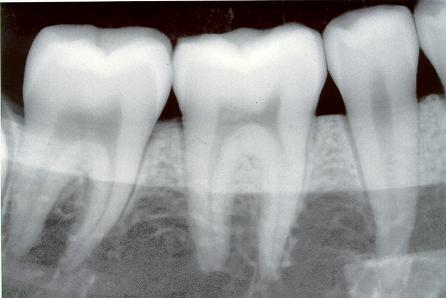

¿Qué debe hacer la próxima vez cuando el dentista le diga que debe tomarse una radiografía dental completa? Un nuevo estudio demuestra que debe limitar la cantidad de exposición a la radiación en el transcurso de la vida, particularmente en los niños.

La Dra. Elizabeth Claus, de la Universidad Yale, reportó en la revista médica “Cáncer” de la Sociedad Americana de Cáncer que existe una relación entre las radiografías dentales y el riesgo de desarrollar tumores de cerebro llamados meningiomas.

Se creía en el pasado que la causa principal de los meningiomas era la ionización de las radiaciones debido a las bombas atómicas o radiaciones recibidas durante el tratamiento del cáncer. Ahora la Dra. Claus dice que el riesgo principal son las radiografías dentales.

La Dra. Claus concluyó que en aquellos que informaron haber tenido radiografías de la boca completa antes de los 10 años, tuvieron 4,9 veces más probabilidades de desarrollar un meningioma. A su vez aquellos que tenían radiografías dentales, de toda la boca, después de los 10 años de edad, tenían un riesgo tres veces mayor. Esto debería destellar como una luz roja para los padres.

Estoy de acuerdo que las radiografías dentales de hoy en día exponen menos radiación que en el pasado. Pero pequeñas cantidades de radiación se acumulan cuando se asciende a la exposición recibida de otras pruebas de rayos X. La radiación no es como una infección que se cura con antibióticos. La radiación es acumulativa, y nuestros cuerpos nunca se olvidan de la cantidad que han recibido en toda la vida.

Por supuesto que las radiografías dentales son necesarias por razones legítimas, pero como todo, puede ser exagerado. Así, que siempre pregunto si la radiografía es realmente necesaria. No se sabe cuánta radiación uno pueda recibir antes de que cause problemas.